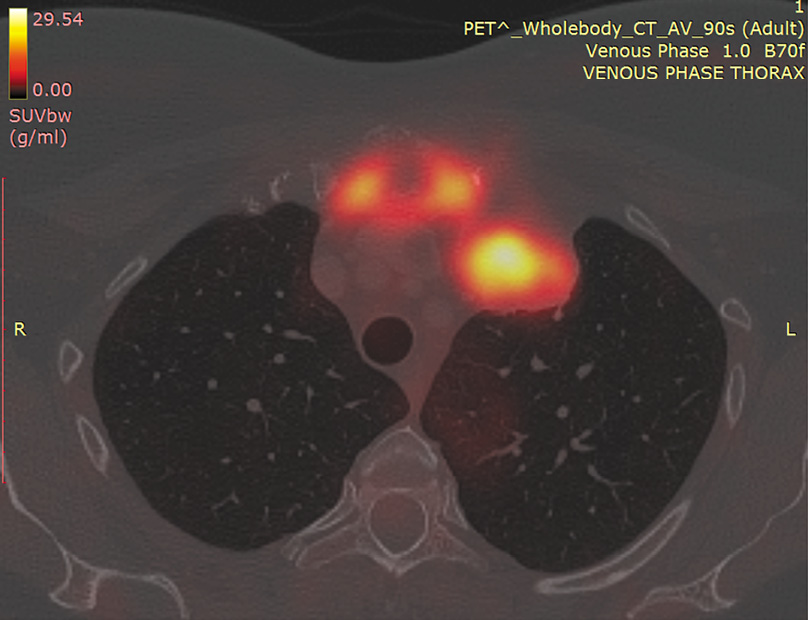

Реконструкция выполнена титановым 3D-протезом, последний фиксирован шурупами и атравматичной нитью к I, II, III ребрам с обеих сторон и к обеим ключицам (рис. 8).

Рис. 8. Конечный вид операции. / Fig. 8. The final type of operation.

Пациентке выполнена операция: резекция рукоятки и тела грудины с резекцией передних отрезков I, II, III ребер с обеих сторон, резекция левой плечеголовной вены, удаление опухоли переднего средостения, атипичная резекция верхней доли левого легкого en bloc, реконструкция грудины и ребер индивидуальным 3D протезом.